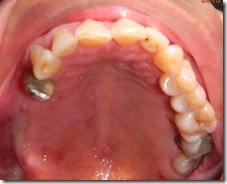

患者A先生

上顎 正面 下顎

患者B小姐

以上兩位患者口內狀況非常複雜,要制定一個好的治療計畫,

不只要考慮到患者的牙齒條件,